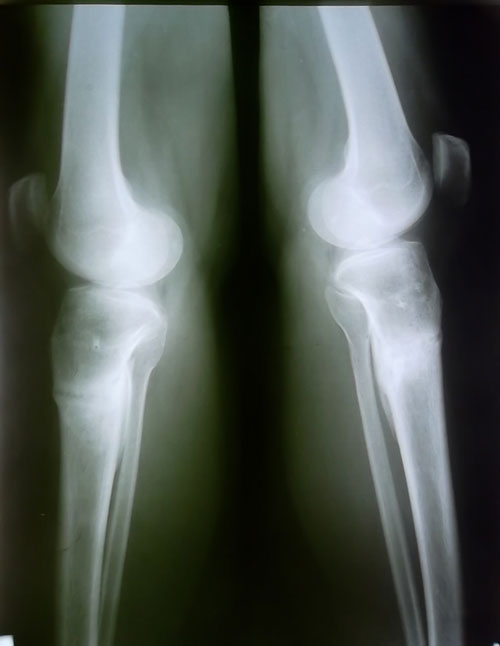

3- я неделя после снятия аппаратов!

Вложения

оспанова-лаура.jpg